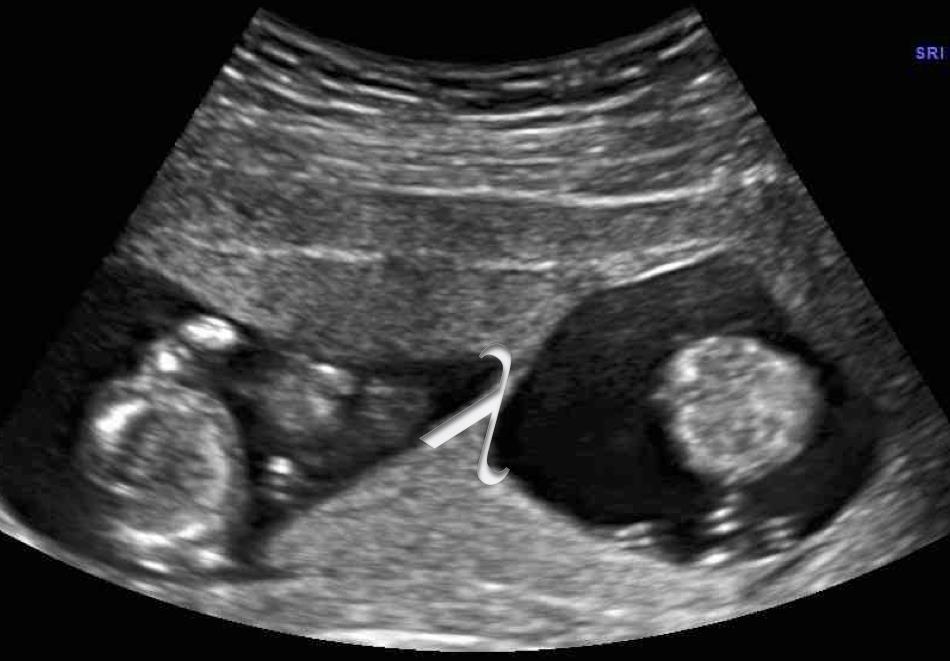

Zwei Babys aber nur eine Plazenta: Früher Ultraschall bei Zwillingsschwangerschaft äußerst wichtig

Berlin – Zwillingsschwangerschaften gelten immer als Risikoschwangerschaften. Das Risiko für Komplikationen erhöht sich, wenn sich beide Zwillinge eine Plazenta – auch Mutterkuchen genannt – teilen. Dies können Ärzte im Ultraschall jedoch nur in der Frühschwangerschaft sicher feststellen, belegt eine aktuelle Studie aus den USA. Die Deutsche Gesellschaft für Ultraschall in der Medizin (DEGUM) empfiehlt Schwangeren, die erste Vorsorge-Ultraschalluntersuchung zwischen der 9ten und 12ten Schwangerschaftswoche unbedingt wahrzunehmen.

„Um das Risiko von Zwillingsschwangerschaften richtig einzuschätzen, ist es wichtig zu wissen, ob sich die Kinder eine Plazenta teilen oder nicht“, erläutert Privatdozent Dr. med. Kai-Sven Heling, Leiter der DEGUM-Sektion Gynäkologie und Geburtshilfe. Stellt der Frauenarzt beim ersten Ultraschall eine Mehrlingsschwangerschaft fest, prüft er daher umgehend ob es sich um „monochoriotische“ Zwillinge handelt, also nur eine Plazenta vorhanden ist – das „Chorion“ bezeichnet den kindlichen Anteil der Plazenta. „Die Bestimmung ist jedoch nur bis zur 14ten Schwangerschaftswoche sicher möglich“, erklärt Heling. Beim zweiten Vorsorge-Ultraschall zwischen der 19ten und 22sten Woche lässt sich der keilförmige Ausläufer des Chorions, der für Schwangerschaften mit zwei Plazenten typisch ist, bereits nicht mehr eindeutig erkennen.

Eine aktuelle Studie von Wissenschaftlern der Stanford University in Kalifornien bestätigt, das der Zeitpunkt des Ultraschalls für die Bestimmung der Chorionizität entscheidend ist. Die Forscher um Yair Blumenfeld hatten bei 545 Frauen, die mit Zwillingen schwanger waren, den Befund des Ultraschalls durch eine Untersuchung der Plazenta nach der Geburt überprüft. Wie die Forscher kürzlich im Fachblatt „Journal of Ultrasound in Medicine“ berichteten, wurde dabei jedes fünfte „monochoriotische“ Zwillingspaar fälschlicherweise als „dichoriotisch“ eingestuft. Die falschen Ergebnisse betrafen vor allem Untersuchungen zwischen der 15. und 20. Schwangerschaftswoche. Bei Untersuchungen bis zur 14. Schwangerschaftswoche lagen nur halb so viele Fehler vor.